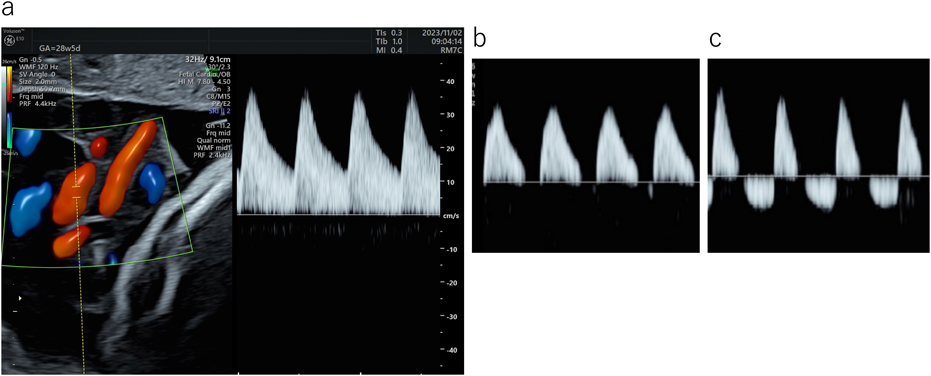

Fig. 6 右室流入血流波形(E/A比)

E/A比は胎児では<1であるが,妊娠週数に伴い増加していく.a:妊娠19週E/A:0.63.b:妊娠28週E/A:0.71.c:妊娠34週E/A:0.77.